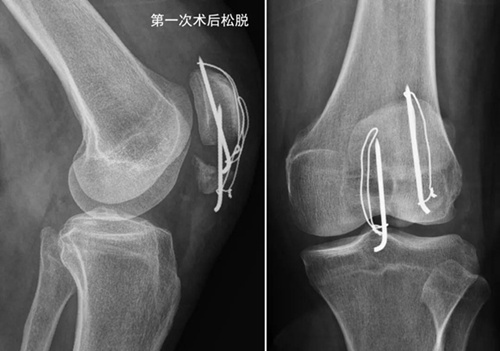

为了避免膝关节术后粘连,洪女士按照康复师的指导,术后即在关节不疼痛的范围活动膝关节,术后2周拆线后加强膝关节的屈伸练习。为了获得良好的膝关节功能,洪女士咬牙克服康复练习的疼痛,没想到练习2周后膝关节肿痛越来越重。体疗师也感到奇怪,建议洪女士拍个片子看看,果然发现钢丝克氏针松脱了,髌骨下极骨折又分开了(如下图)。